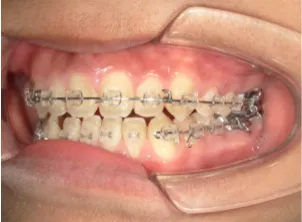

治療中④中2:マルチブラケット法へ移行:上下正中を合わせたい

*マルチブラケット法

治療後⑤中3:咬合治療終了 マルチブラケット法の期間は9か月